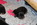

seid kurzem sind wir wieder glückliche Besitzer eines Top Ultraschallgerätes, Danke noch mals an Pelin und Hanno(Bertie/Oskar leben). Wir sind so glücklich. Es ist sehr leicht und man kann es mitnehmen und einfach durch die Zimmer schieben.

Normalerweise hat jede Hündin einen Trächtigkeitsverlauf.

Bei Fae fehlte mir die Zeit, leider. Unten in der Galerie sieht man ihre Zunahmen mit Bildern.

Startgewicht 8,6 kg

26.Tag  8,6kg

35.Tag 9150g  +550g

41.Tag 9650g +1040g

47.Tag  1010g +1410g

52.Tag 10350g +1750g

56.Tag  10640g +2046g

Man rechnet ungefähr pro Welpe mit Fruchthülle,Fruchtwasser und Plazenta 500g.

Das stimmt nicht immer, hier stimmt es genau.

Ich habe sie fast täglich gewogen, hier nur ein Paar Ergebnisse zur Anschauung.